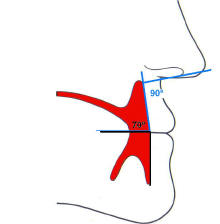

"La dimensión vertical

oclusiva es la distancia entre el

maxilar y la mandíbula cuando los

rodetes están en contacto entre si

en posición de relación céntrica."

Ver imagen derecha

3- Cumplidos los requisitos del paso anterior; verifique la altura

de la

dimensión vertical oclusiva. |

- Esto se realiza comparando la altura facial

inferior del paciente que es la línea que va del mentón hasta la

base de la nariz y debe ser proporcional al tercio medio de la cara

de nuestro paciente, que es el segmento

comprendido entre la base de la nariz y la glabela. (Regla de los

tres tercios)